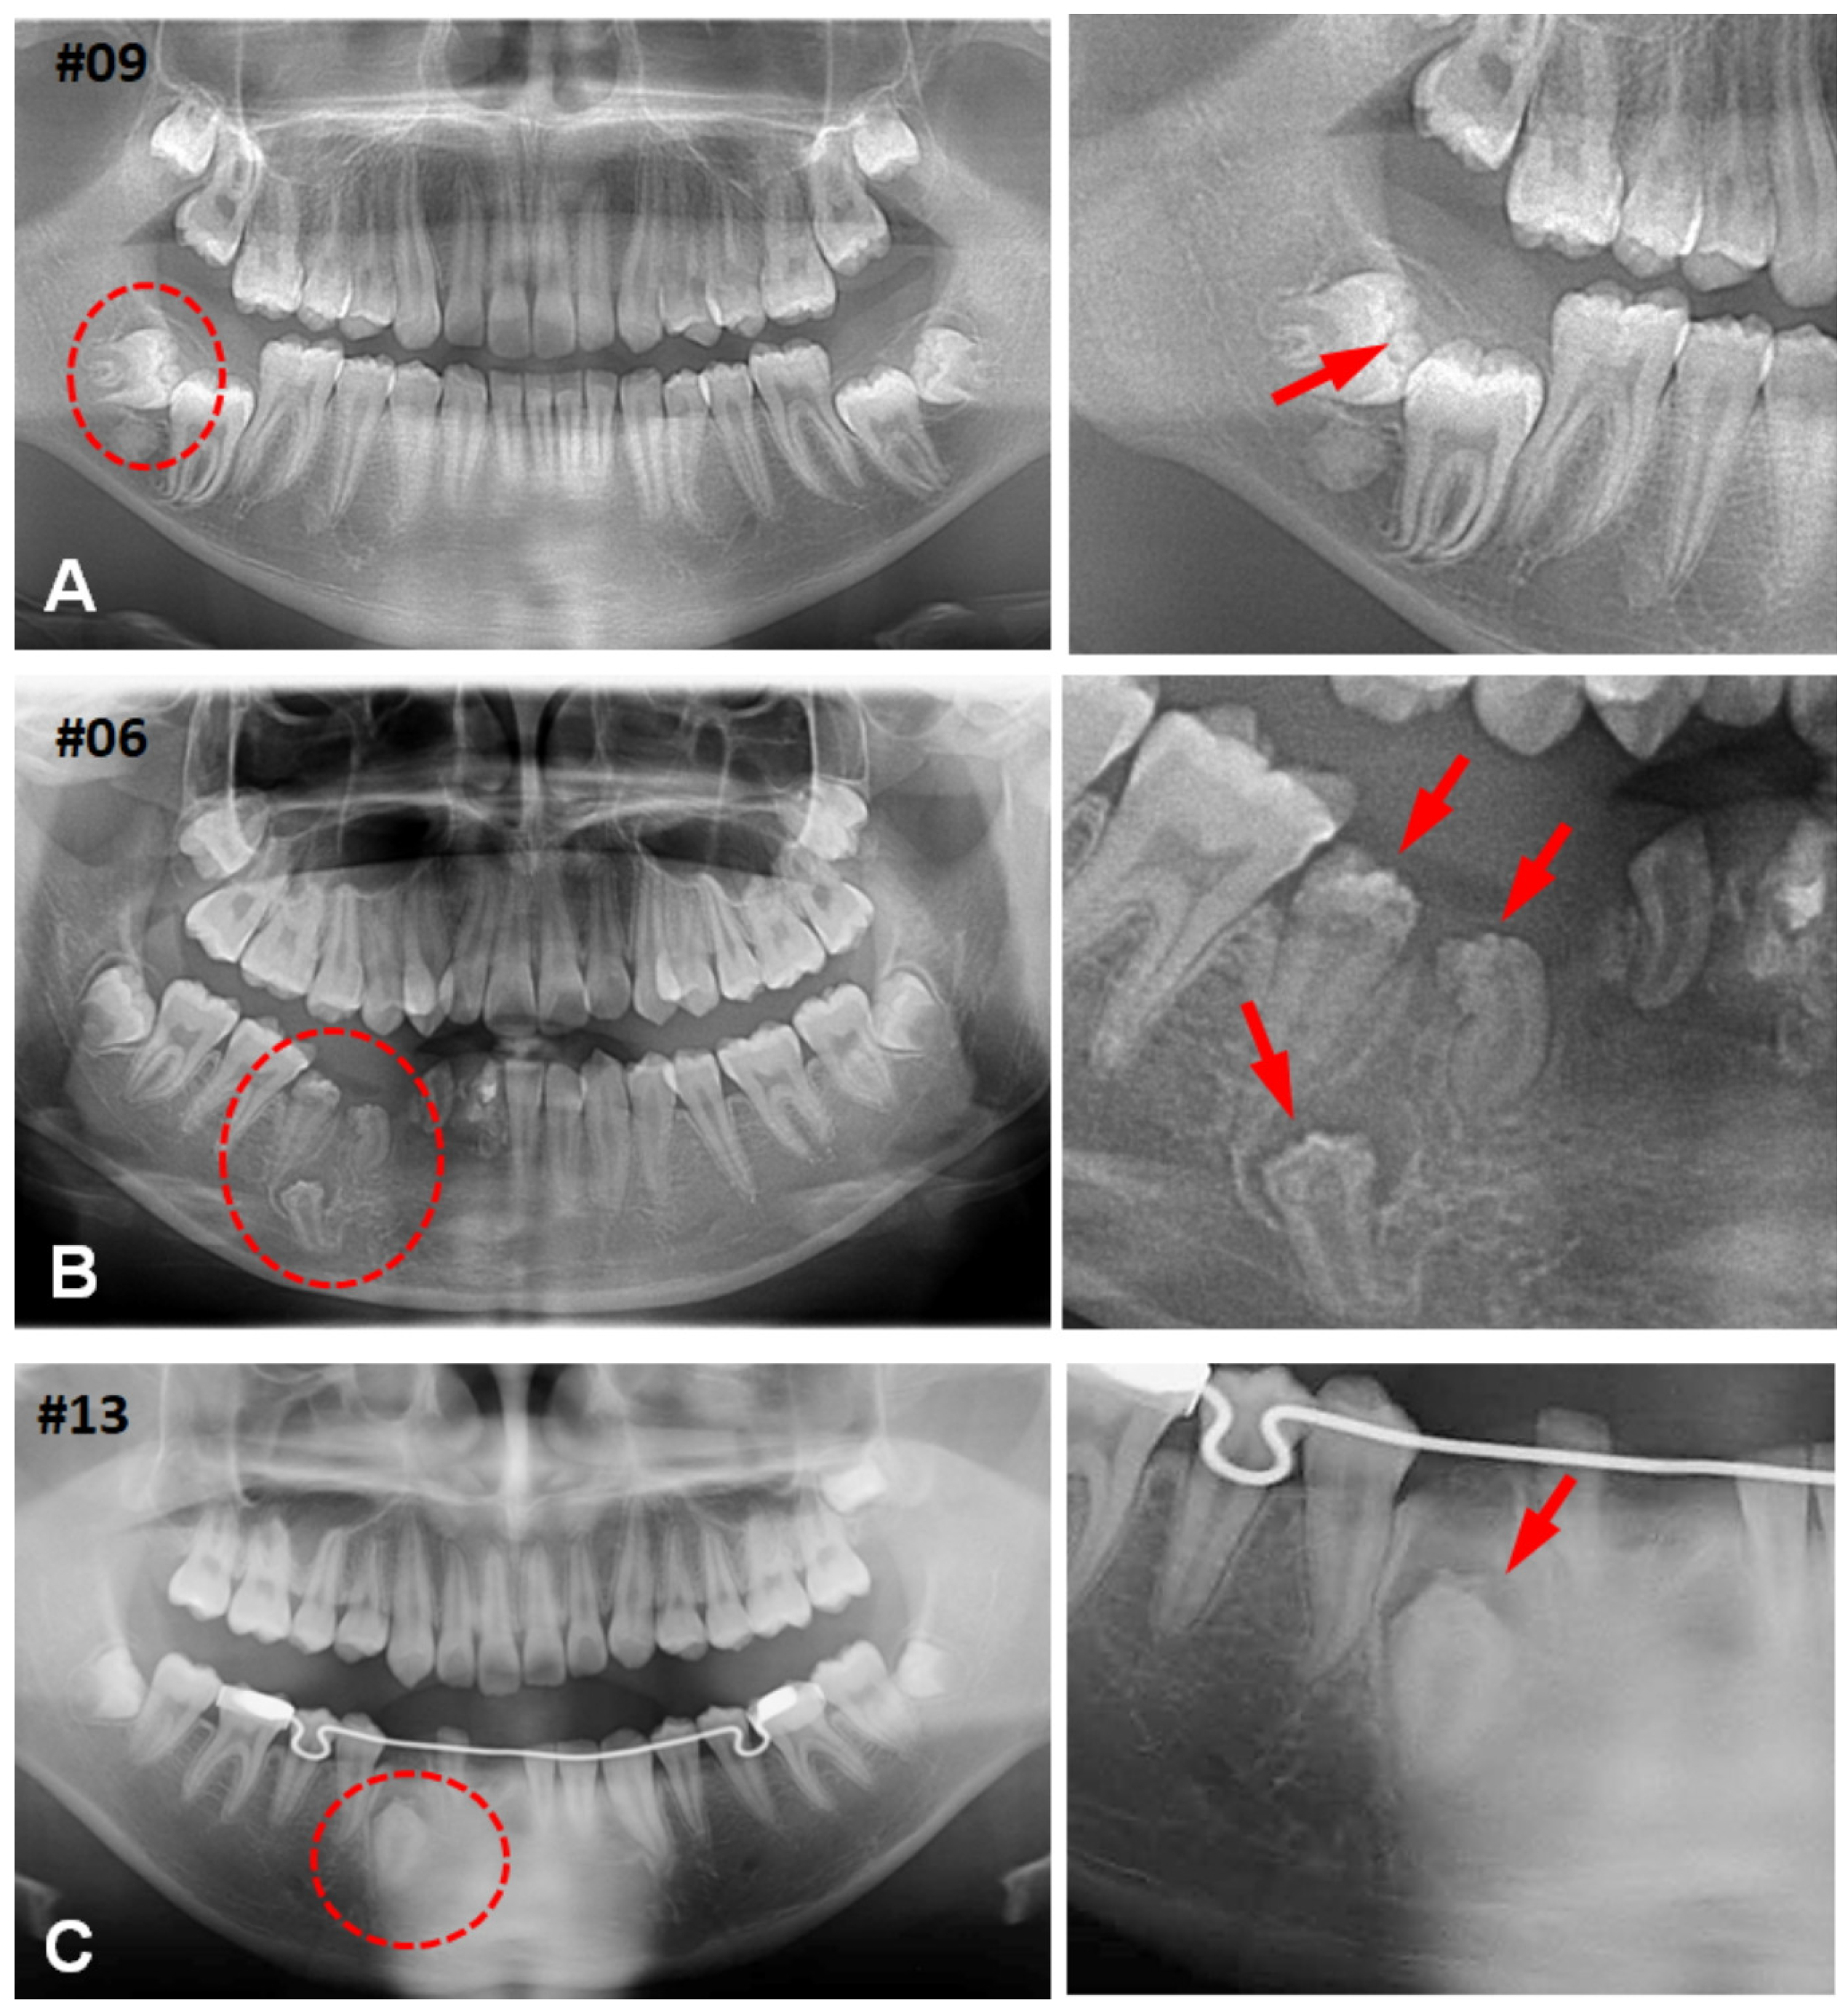

3.1. Clinical Characteristics of CHDFs